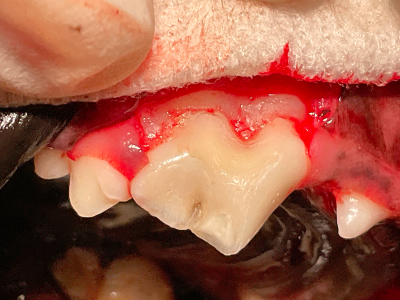

歯肉を切開・剥離してから全体を修復します。